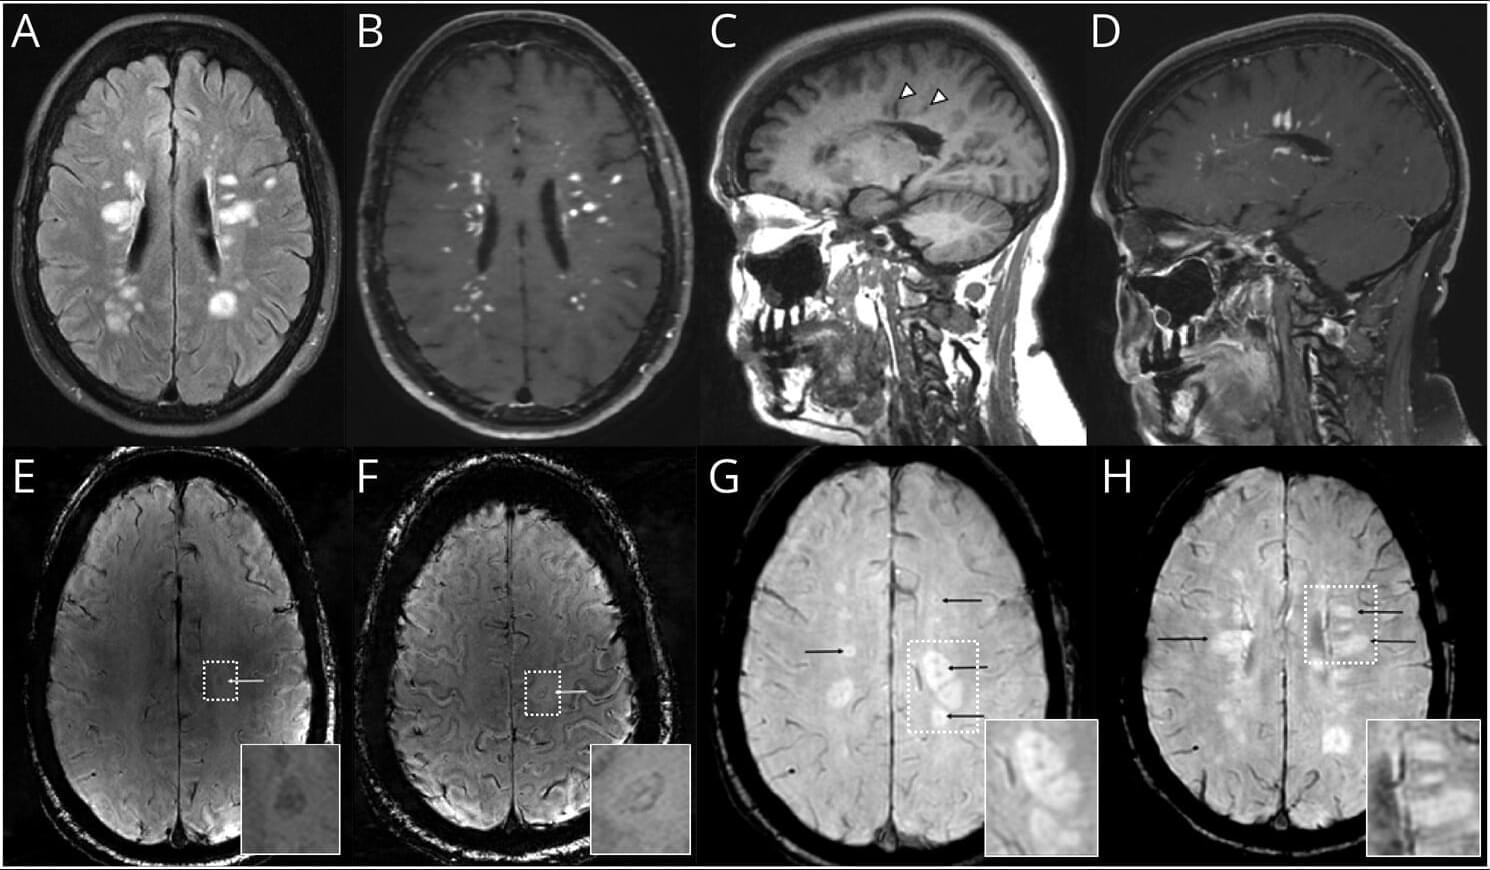

Central vein sign and paramagnetic rim lesions can aid in an earlier diagnosis of late-onset multiple sclerosis and may circumvent the need for biopsy. Learn more in this Pearls & Oy-sters article.